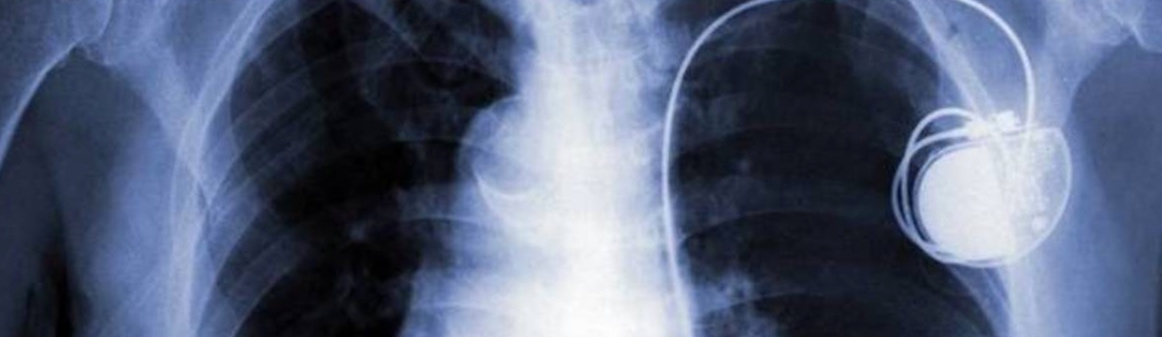

Pacemaker potentiellement piratable, et si on arrêtait de paniquer ?

Donc, pour résumer, la FDA (Food and Drog Administration) a lancé une joyeuse alerte en affirmant de “potentiels problèmes de sécurité avec certains pacemakers“. Evidemment, tout le monde a commencé à paniquer et, Facebook aidant, l’information est vite partie en sucette sans que personne ne s’aperçoive du fond du problème.

Pour en revenir à la source de cet appel à la vigilance de nos amis américains en manque de Barack (Fraiture… Comprenne qui pourra, et surtout pas nos amis français), la FDA a simplement détecté que le moniteur de la marque Merlin était potentiellement “hackable”. Il s’agit du transmetteur Merlin@home conçu par l’entreprise St. Jude Medical qui envoie les informations du patient dans le Cloud. Ces données peuvent être consultées par le brave médecin qui pourra ensuite adapter le rythme du pacemaker.

Vous l’aurez compris, si cette chaine venait à être piratée, les informations se trouvant sur le Cloud ne pourraient donc pas refléter les données réelles et le médecin pourrait donc adapter la configuration du pacemaker de façon tout à fait erronée.

En conclusion, pas de panique, le fabricant a déjà mis en place un correctif qui ferme toutes les portes à de belliqueuses personnes qui passent leur temps à pirater ce genre de dispositif, c’est bien connu. Si vous avez un parent qui en possède un, allez donc le rassurer : tout va bien ! Si vous êtes la compagne d’un coeur faiblard, allez donc faire un tour chez Hunkemoller, les soldes sont toujours d’actualité.